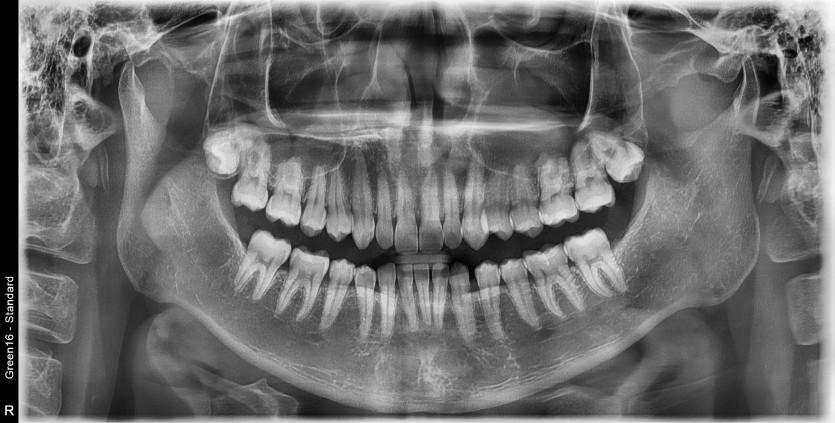

#28 사랑니 발치

구강 외과 전문의가 당일 발치했습니다.-----------------------------------------------------------------------------------------------------------------------------------